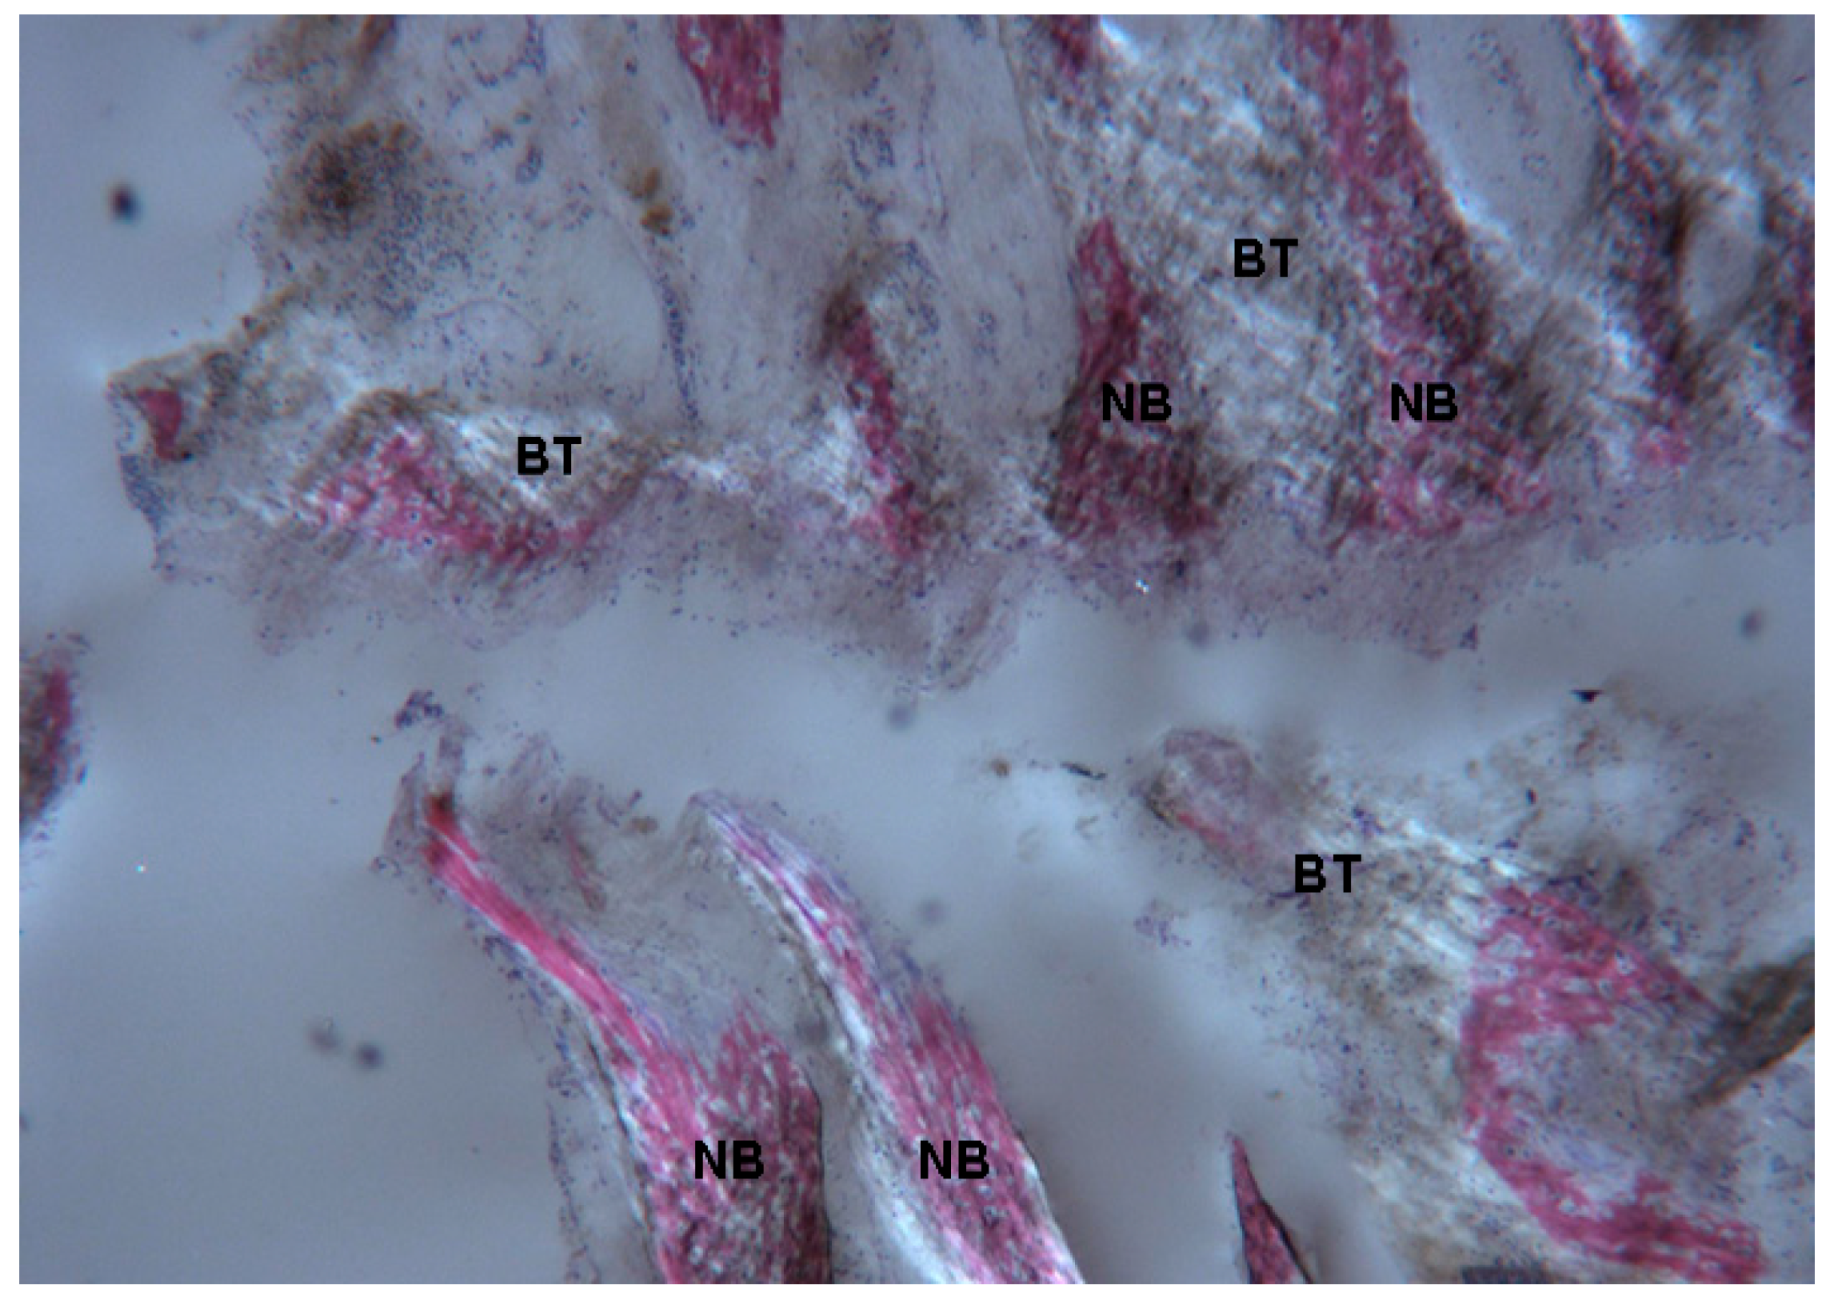

2.1. Histological Results

2.1.3. Test at 30 Days (Subject 2, Male)

2.2. Polarized Light

2.2.3. Test at 30 Days (Subject 2, Male)